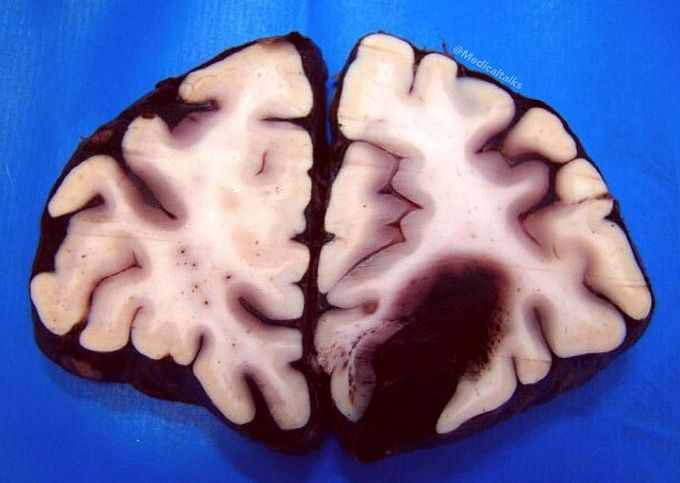

Gross specimen of a brain, frontal section, showing a cerebral hemorrhage (cerebrovascular accident) of the left hemisphere in a patient with hypertension!! There is a large hematoma with mass effect. Hemorrhages involving the basal ganglia area (the putamen in particular) tend to be non-traumatic and caused by hypertension, which damages and weakens the small penetrating branches of the major cerebral arteries. The resulting spontaneous deep intracerebral bleeding caused a mass effect with midline shift, often with secondary edema, may disrupt or compress adjacent brain tissue, leading the neurological dysfunction. Substantial displacement of brain parenchyma may cause elevation of intracranial pressure and potentially fatal herniation syndromes. Nontraumatic intracerebral hemorrhage most commonly results from hypertensive damage to blood vessel walls (eg, hypertension, eclampsia, drug abuse), but it also may be due to autoregulatory dysfunction with excessive cerebral blood flow (eg, reperfusion injury, hemorrhagic transformation), rupture of an aneurysm or arteriovenous malformation, or arteriopathy (eg, cerebral amyloid angiopathy, moyamoya). Nonsurgical management is considered for patients with minimal neurological deficits or with intracerebral hemorrhage volumes less than 10 mL. Surgery is preserved for patients with cerebellar hemorrhage greater than 3 cm, for patients with intracerebral hemorrhage associated with a structural vascular lesion, and for young patients with lobar hemorrhage.